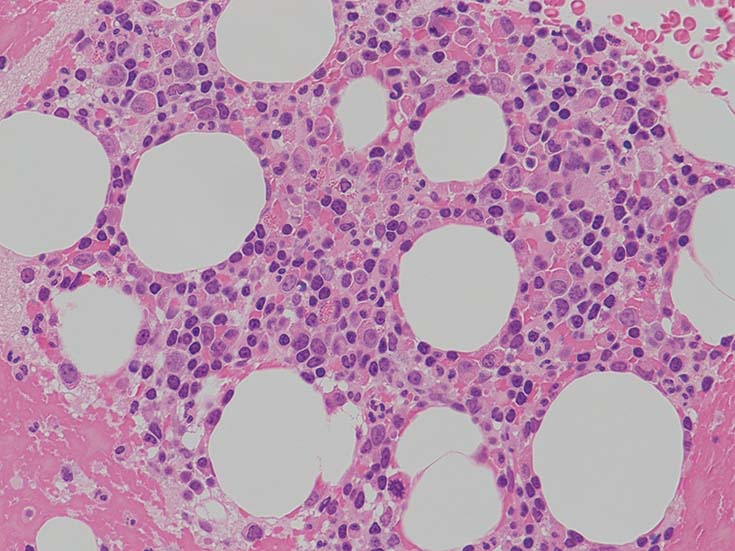

この症例では骨髄組織での造血巣内にリンパ球や形質細胞の軽度増加があるようだが, 腫瘍細胞増殖が明瞭ではない. 結節形成はみられない. mast cellsの増加がNaphtol-ASD-CAE染色で確認される.